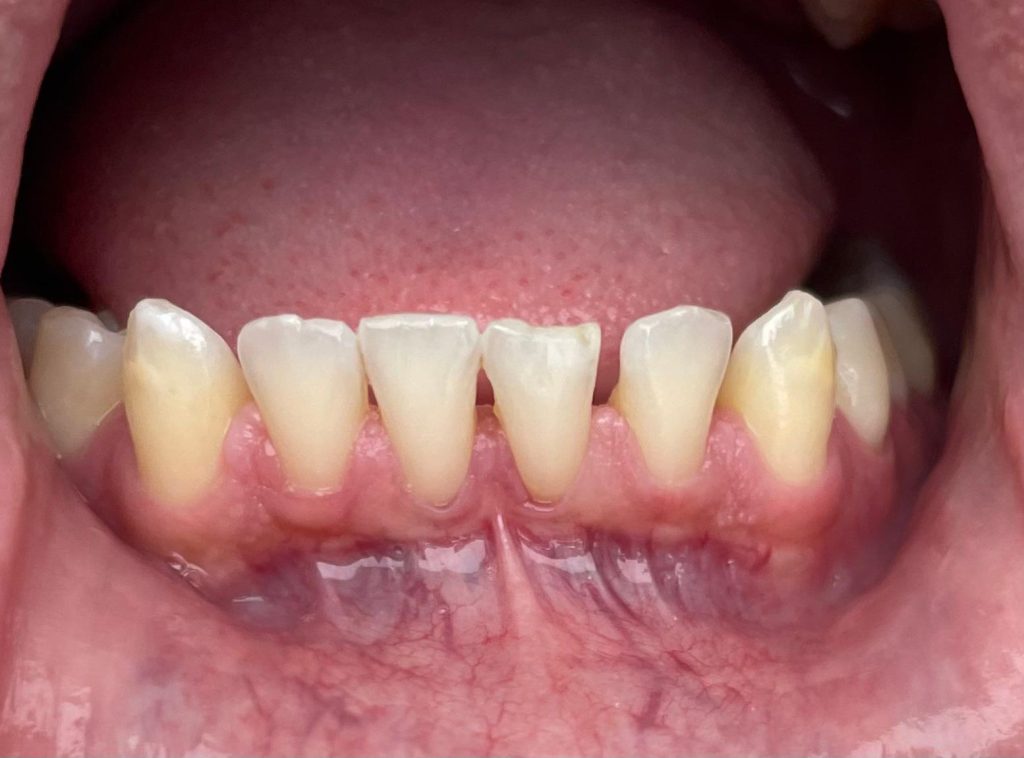

Questa settimana vi presentiamo il caso di frenulectomia del labbro superiore e inferiore eseguita con un laser KTP.

Nelle immagini, oltre alle fasi dell’intervento, è possibile osservare la guarigione dei tessuti dopo 10 giorni.